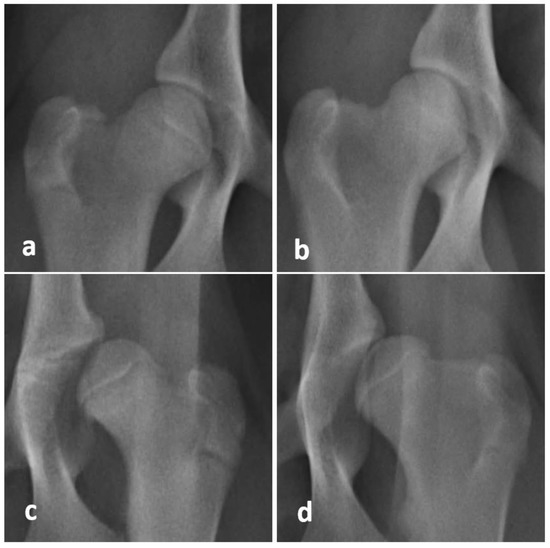

2.3. Orthopedic Hip Examinations under General Anesthesia

2.3.1. Barlow Maneuver

2.3.2. Ortolani Maneuver

2.3.3. Bardens Maneuver